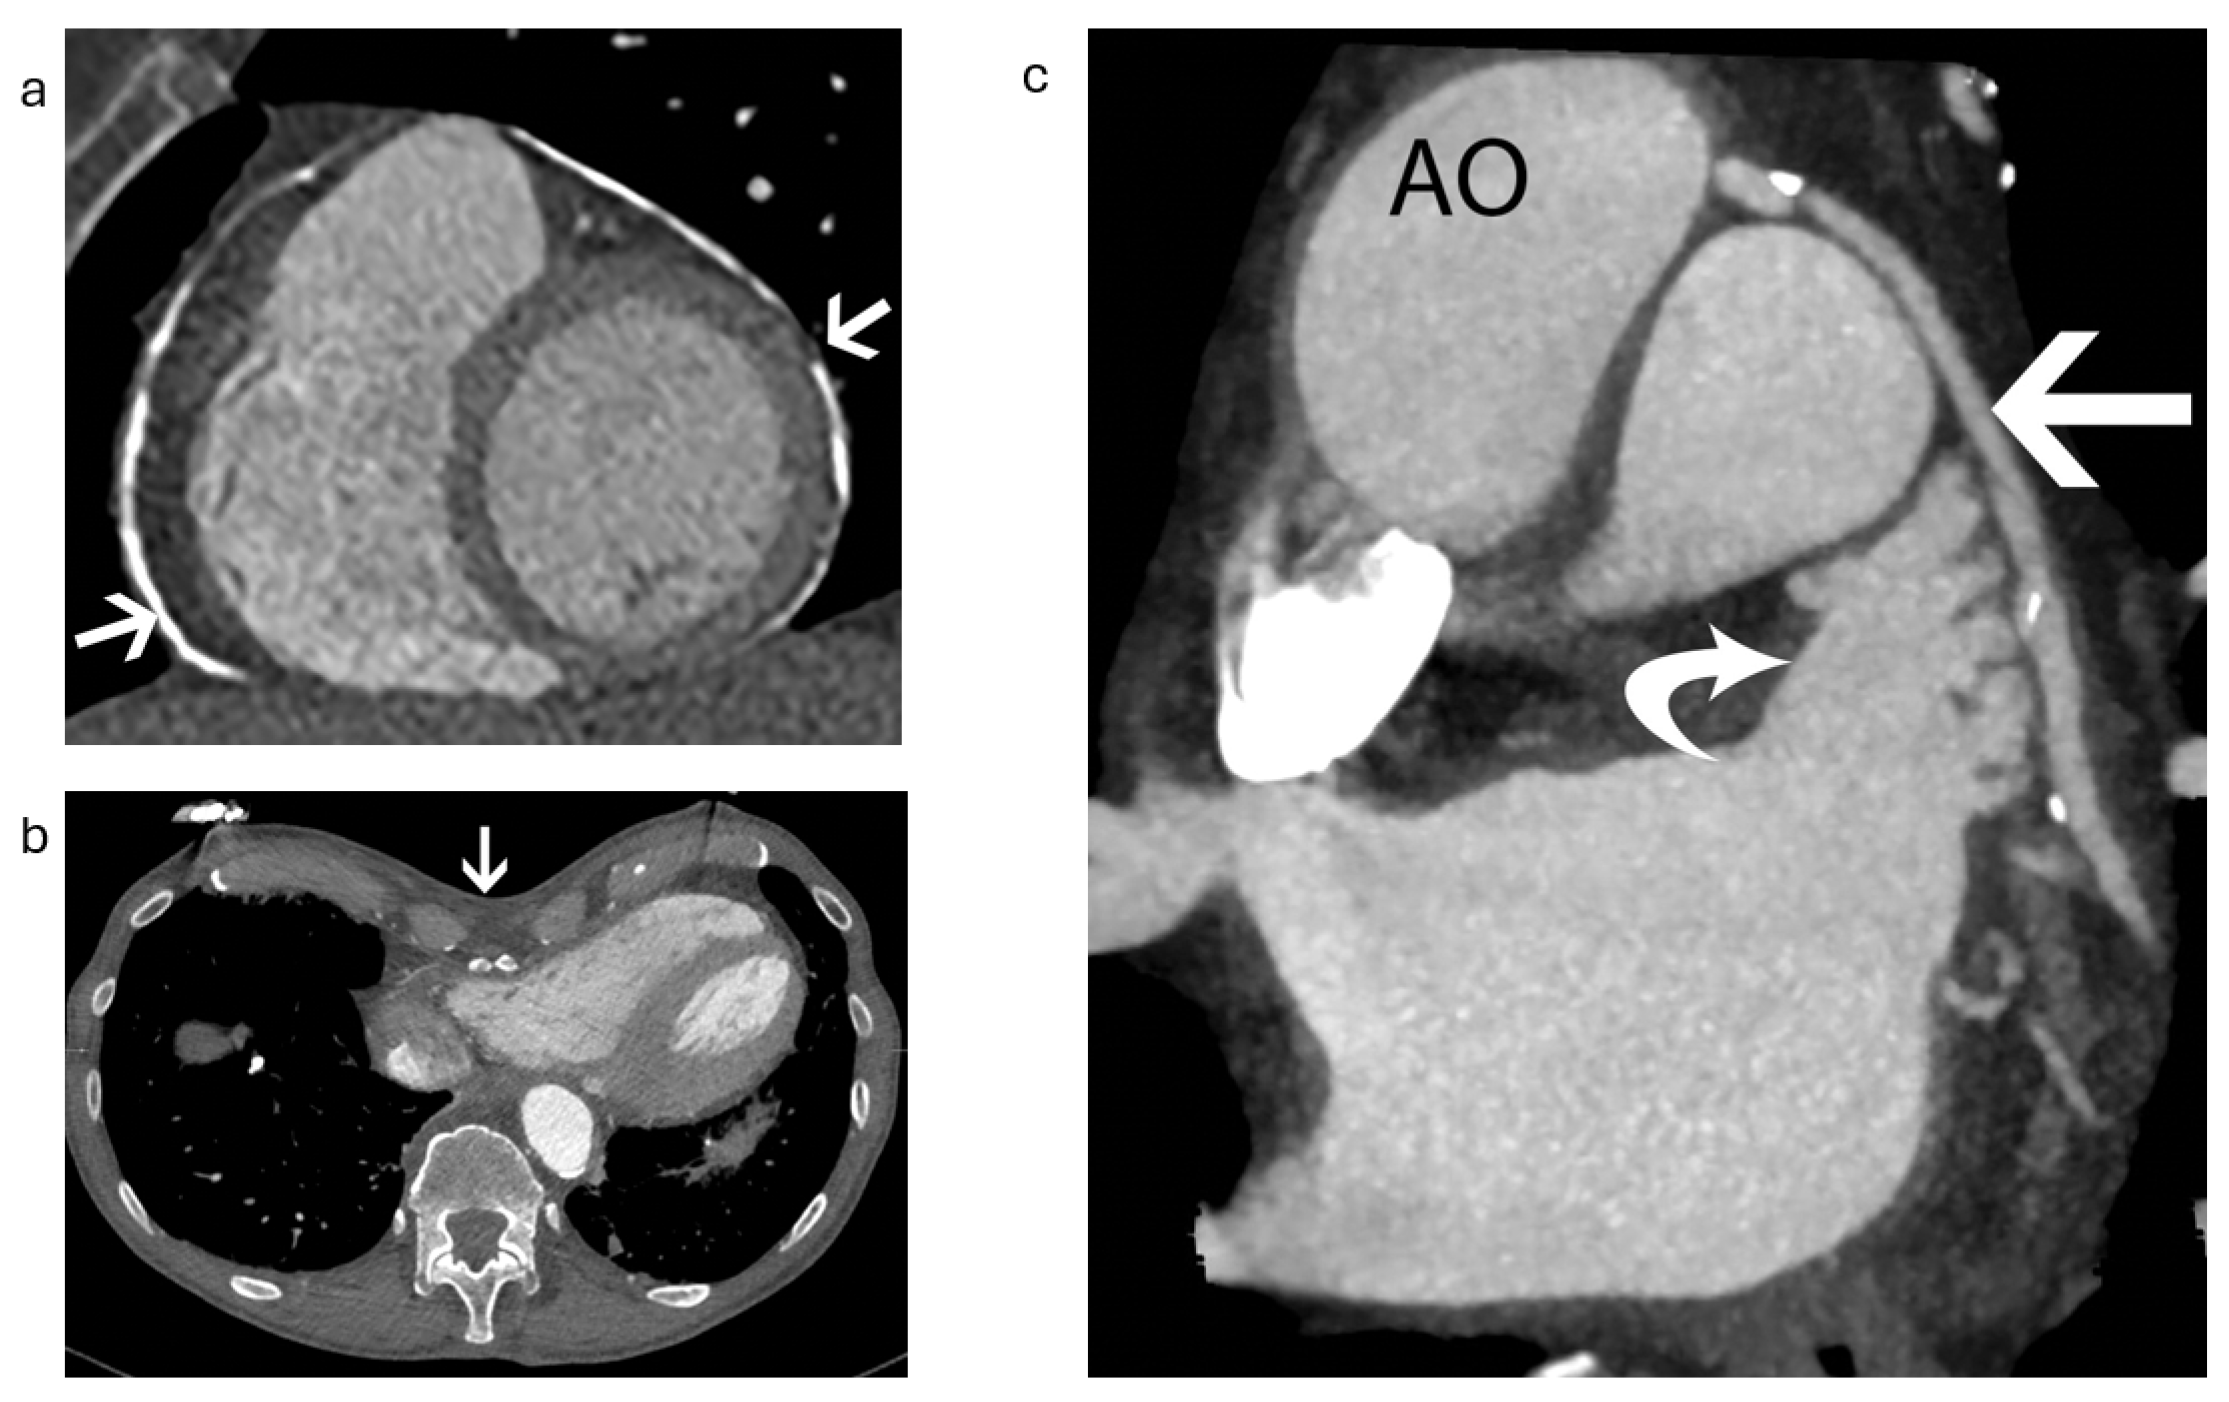

2.1.1. Anatomical Contraindications

2.1.2. LAA Measurements

2.1.3. Assessment of the Inter-Atrial Septum

2.1.4. Other Anatomical Considerations